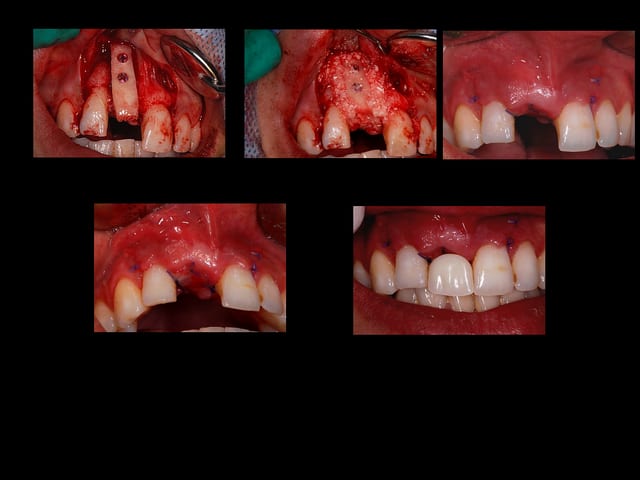

Planche1 nb4u3t - Eugenol

Planche2 awlu7r - Eugenol

et bloc biobank?.... growler a montré plusieurs cas qui ont très bien fonctionné

pour ma part,jreviens sur une greffe biobank dans 15 jours...je pourrais te dire ce que j en pense

c est un bloc biobank?

> c est un bloc biobank?

oui.

ici, les particules sont de la poudre d'os spongieux de 0.5 mm biobank

la corticale du greffon fait à peu près un mm d'épaisseur et la partie spongieuse garde une consistance solide.